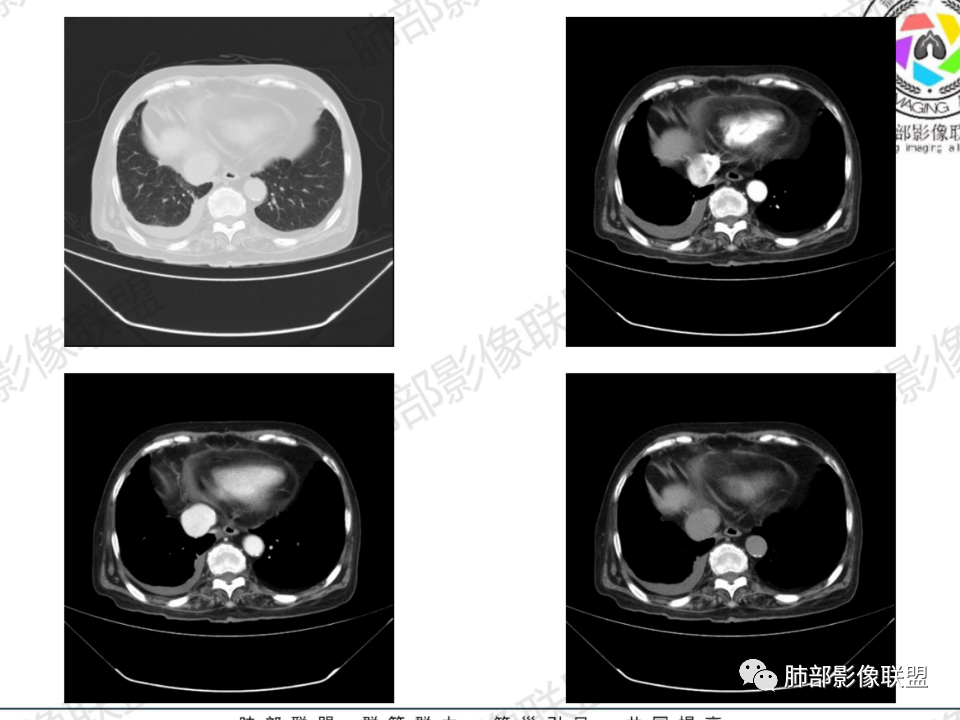

那个人:老年女性,亚急性病程,咳嗽发热。有垂体前叶功能减退,目前激素替代治疗,长期激素,量小,不知道累积量,没有目前激素水平指标。既往有淋巴结结核病史。肿瘤标记物Ca125升高。血沉升高,C反应蛋白轻度异常。影像,右肺上叶靠近肺门团块影,右肺门淋巴结钙化肿大,支气管狭窄,局部增厚,团块影外朝内改变,强化明显,血管破坏不明显,有粘液。和纵隔胸膜分界清楚,周围肺组织有斑片渗出影,右侧胸腔积液,考虑炎性?结核?支气管镜检查除外恶性飞鹰行动:老年患者,影像表现 右肺上叶占位性病变,边界清楚,有分叶征,内见细小钙化,右肺上叶支气管截断,增强病灶不均匀强化,病灶内有条状坏死区(扩张的支气管?),纵膈内未见增大淋巴结,考虑炎性病变,结核可能。一切∮随缘:右肺上叶实性肿块形态不规则,呈三角形,边缘分叶,边界伴有磨玻璃影,近段支气管未见明显显示,可能堵塞,病变平扫密度均匀,增强后可见低密度坏死无强化,周围略强化,右肺下叶散在结节。心包积液,及右侧胸腔积液,临床:有低热,低蛋白血症,肿瘤标记物高,考虑恶性:腺癌,神经内分泌癌(强化偏弱了),淋巴瘤,鉴别:结核红星:老年女性患者右肺上叶,肺门上区 分叶状肿块 ,右肺上叶支气管显示不清,增强扫描肿块,中等程度强化可见小斑片状坏死区,病灶内部可见斑点状钙化灶,病灶周围可见斑片状及小斑点状影,纵膈淋巴结增大,其他区域,胸膜下可见斑点状钙化。考虑肉芽肿性病变,结核的可能性大。老年患者最排除肿瘤性病变腺癌。土娃:右上肺不规则肿块影,边缘分叶,边界磨玻璃影欠清,病灶分叉状,内见点状钙化影及坏死灶,支气管堵塞,病灶增强强化不明显。考虑瘤样结核,鉴别淋巴瘤。张小兵:老年女性,亚急性病程,右肺上叶见不规则肿块,边缘平直凹陷为主,周围GGO边界不清,内见点状钙化及坏死灶,增强持续性渐进强化,右侧少量胸腔积液,双肺门及纵隔肿大淋巴结伴钙化,综合考虑慢性炎症。saf:老年患者,影像表现 右肺上叶占位性病变,边界清楚,有分叶征,增强病灶明显不均匀强化,纵膈内未见增大淋巴结,考虑炎性病变,结核可能。小兜:老年女性,咳嗽喘息一月,发热三天,肿瘤标志物升高,长期激素替代治疗。CT示右肺上叶近肺门不规则实变影,周围伴磨玻璃影,增强持续性渐进强化,内部血管破坏不厉害,内部可见多发条形低密度灶,右侧胸腔可见少量积液,双肺门及纵隔可见钙化淋巴结,考虑为炎性病变,结核可能玫:女,79咳嗽,喘息一月,发热三天入院,右肺上叶不规则形软组织密度肿块影,边界清晰,边缘见分叶及细短毛刺,病灶内见点状钙化影及稍低密度区,病灶边缘呈磨玻璃样改变,增强扫描,病灶呈不均匀性强化,考虑炎性病变,鉴别鳞癌。大雄:老年女性,既往诊断淋巴结结核,提示已治愈,近2年服用激素,诱导结核复燃→发热;纵隔肺门淋巴结肿大钙化,压迫支气管,右肺上中下叶支气管均狭窄→喘息咳嗽;尖段支气管受累闭塞→肺不张、支气管粘液栓;累及胸膜,结核性胸膜炎并胸水→右侧胸痛;实验室,血沉快,CA125高,低蛋白,符合;下一步,支气管镜尖段支气管刷检抗酸染色周太狼:老年女性,亚急性病程,肿瘤标志物升高。CT示右肺上叶尖段不规则肿块影,有分叶、收缩,周围伴磨玻璃影,增强渐进强化,内部可见多发条形低密度灶,右侧胸腔及心包少量积液,纵隔内淋巴结稍增大。倾向于恶性病变,肺癌伴阻塞性炎变可能。丽:老年女性,右肺上叶不规则软组织肿块,边缘清晰,内密度不均,可见点状钙化及粘液栓,周围可见片状高密度影,增强后均匀强化,内多发低密度,纵膈多发钙化淋巴结,考虑结核可能大,建议结合支气管镜检查除外肿瘤宇宙:右胸廓缩小,右肺上叶团块影及不张,平直边,周围磨玻璃影,纤细胸膜牵拉,上叶尖段支气管堵塞,明显延迟强化,可见支气管粘液栓,两肺门钙化淋巴结,右侧胸水,考性炎性肉芽肿,鉴别腺癌王秀仙:右肺上叶肺门区肿块,上叶支气管开口阻塞,形态不规则,密度不均,内可见支气管粘液栓及多发小灶性坏死,周围磨玻璃影边缘模糊,渐进强化,右侧胸腔积液、胸膜钙化,考虑炎性肉芽肿性病变,慢性炎症。鉴别鳞癌,结核。刘丹:老年女性,右肺上叶肿块伴钙化,右肺上叶支气管截断,增强后均匀强化,周边可见点片状模糊影,右侧胸腔积液,右肺门淋巴结增大,考虑占位并阻塞性炎症,肿瘤?结核?建议纤支镜检查。小飞:右肺上叶纵隔旁软组织肿块,边缘深分叶、长毛刺及毛刷样短毛刺,边缘磨玻璃影,磨玻璃边界模糊,支气管截断,平扫密度不均,可见点状钙化,增强不均匀明显强化,心影增大,心包积液,右侧胸腔积液,考虑恶性肿瘤,腺癌?秦化君:右肺上叶不规则分叶软组织密度肿块,边缘清晰,胸膜牵拉,周围花花草草,上叶尖段支气管阻塞,内可见点状钙化,增强后密度不均可见支气管粘液栓及坏死区,内见血管分枝。中间段及中叶,下叶支气管狭窄,壁见钙化。右肺门淋巴结肿大,右侧胸腔积液,心包粘连肥厚。考虑1右上肺恶性病变,鳞癌?2右肺多叶段支气管狭窄,考虑支气管内膜结核?3胸腔积液及肺门淋巴结肿大,转移?风儿:老年女性,右肺上叶肿块,形态不规则,外围大内带小,边缘分叶膨隆平直及毛糙,密度不均,内见支气管粘液栓及多发小灶性坏死,坏死边缘清晰 ,渐进强化,上叶尖段支气管阻塞,叶支气管壁有局限性增厚,邻近胸膜腔微积液;纵隔及双肺门淋巴结肿大,部分钙化,右侧胸腔积液、心包积液、胸膜钙化,考虑炎性,肉芽肿性结核可能性大。鉴别鳞癌,女性及血供均不支持;腺癌,坏死边界太清晰。流心明智:老年女性,79岁,咳嗽、气短1月,发热3天。胸CT:右肺上叶见不规则肿块,边缘有膨隆、有平直凹陷,周围GGO边界不清,病灶内见点状钙化、粘液栓,尖段支气管未见,增强持续性渐进强化,右侧少量胸腔积液,双肺门及纵隔肿大淋巴结伴钙化,肺动脉增粗。考虑:右上叶尖段堵塞并慢性炎症,支气管TB并结石?鉴别Ca

胸腔积液并胸膜钙化,符合结核;

临床信息:老年女性,亚急性病程,咳嗽发热。有激素使用史。既往有淋巴结结核病史。肿瘤标记物Ca125升高。血沉升高,C反应蛋白轻度异常。 影像所见:右侧胸廓相对狭小,右肺上叶不规则团块影贴附纵隔旁,轻度分叶,整体密度较均匀,偶见钙点。

相应上叶尖端及前段支气管开口未能追踪(阻塞),开口处见钙化。病灶渐进性强化,并衬托出较完整尖段及前段含液支气管影。支气管开口区域未见异常高密度强化(如类癌等)及相对乏血供区(如鳞癌)。病灶区未见液化坏死。右上纵隔及胸廓入口区未见病灶胸膜外突破(栽赃)。

右肺上叶后段等区域散在片状影,边界不清(提示渗出性病灶)。

纵隔及双肺门见钙化淋巴结。心包积液,右侧胸腔积液(提示存在活动新病灶)。双侧胸膜下见多发斑点状钙化,胸廓变形(提示存在结核基础病变可能)。 诊断意见:综上,右肺上叶块状影更符合继发性肺结核。 最后小结:既往诊断淋巴结结核,提示已治愈。近2年服用激素,可疑诱导结核复燃,也可引起发热。纵隔肺门淋巴结肿大钙化,压迫支气管,右肺上中下叶支气管均狭窄,所以引起喘息咳嗽。尖段支气管受累闭塞,导致肺不张、支气管粘液栓,出现条状无强化区。病变累及胸膜,导致结核性胸膜炎并胸水,引起右侧胸痛。实验室检查血沉快,CA125高,低蛋白,均符合结核。下一步,建议支气管镜尖段支气管刷检并抗酸染色。(本段摘自於雄老师精彩发言)